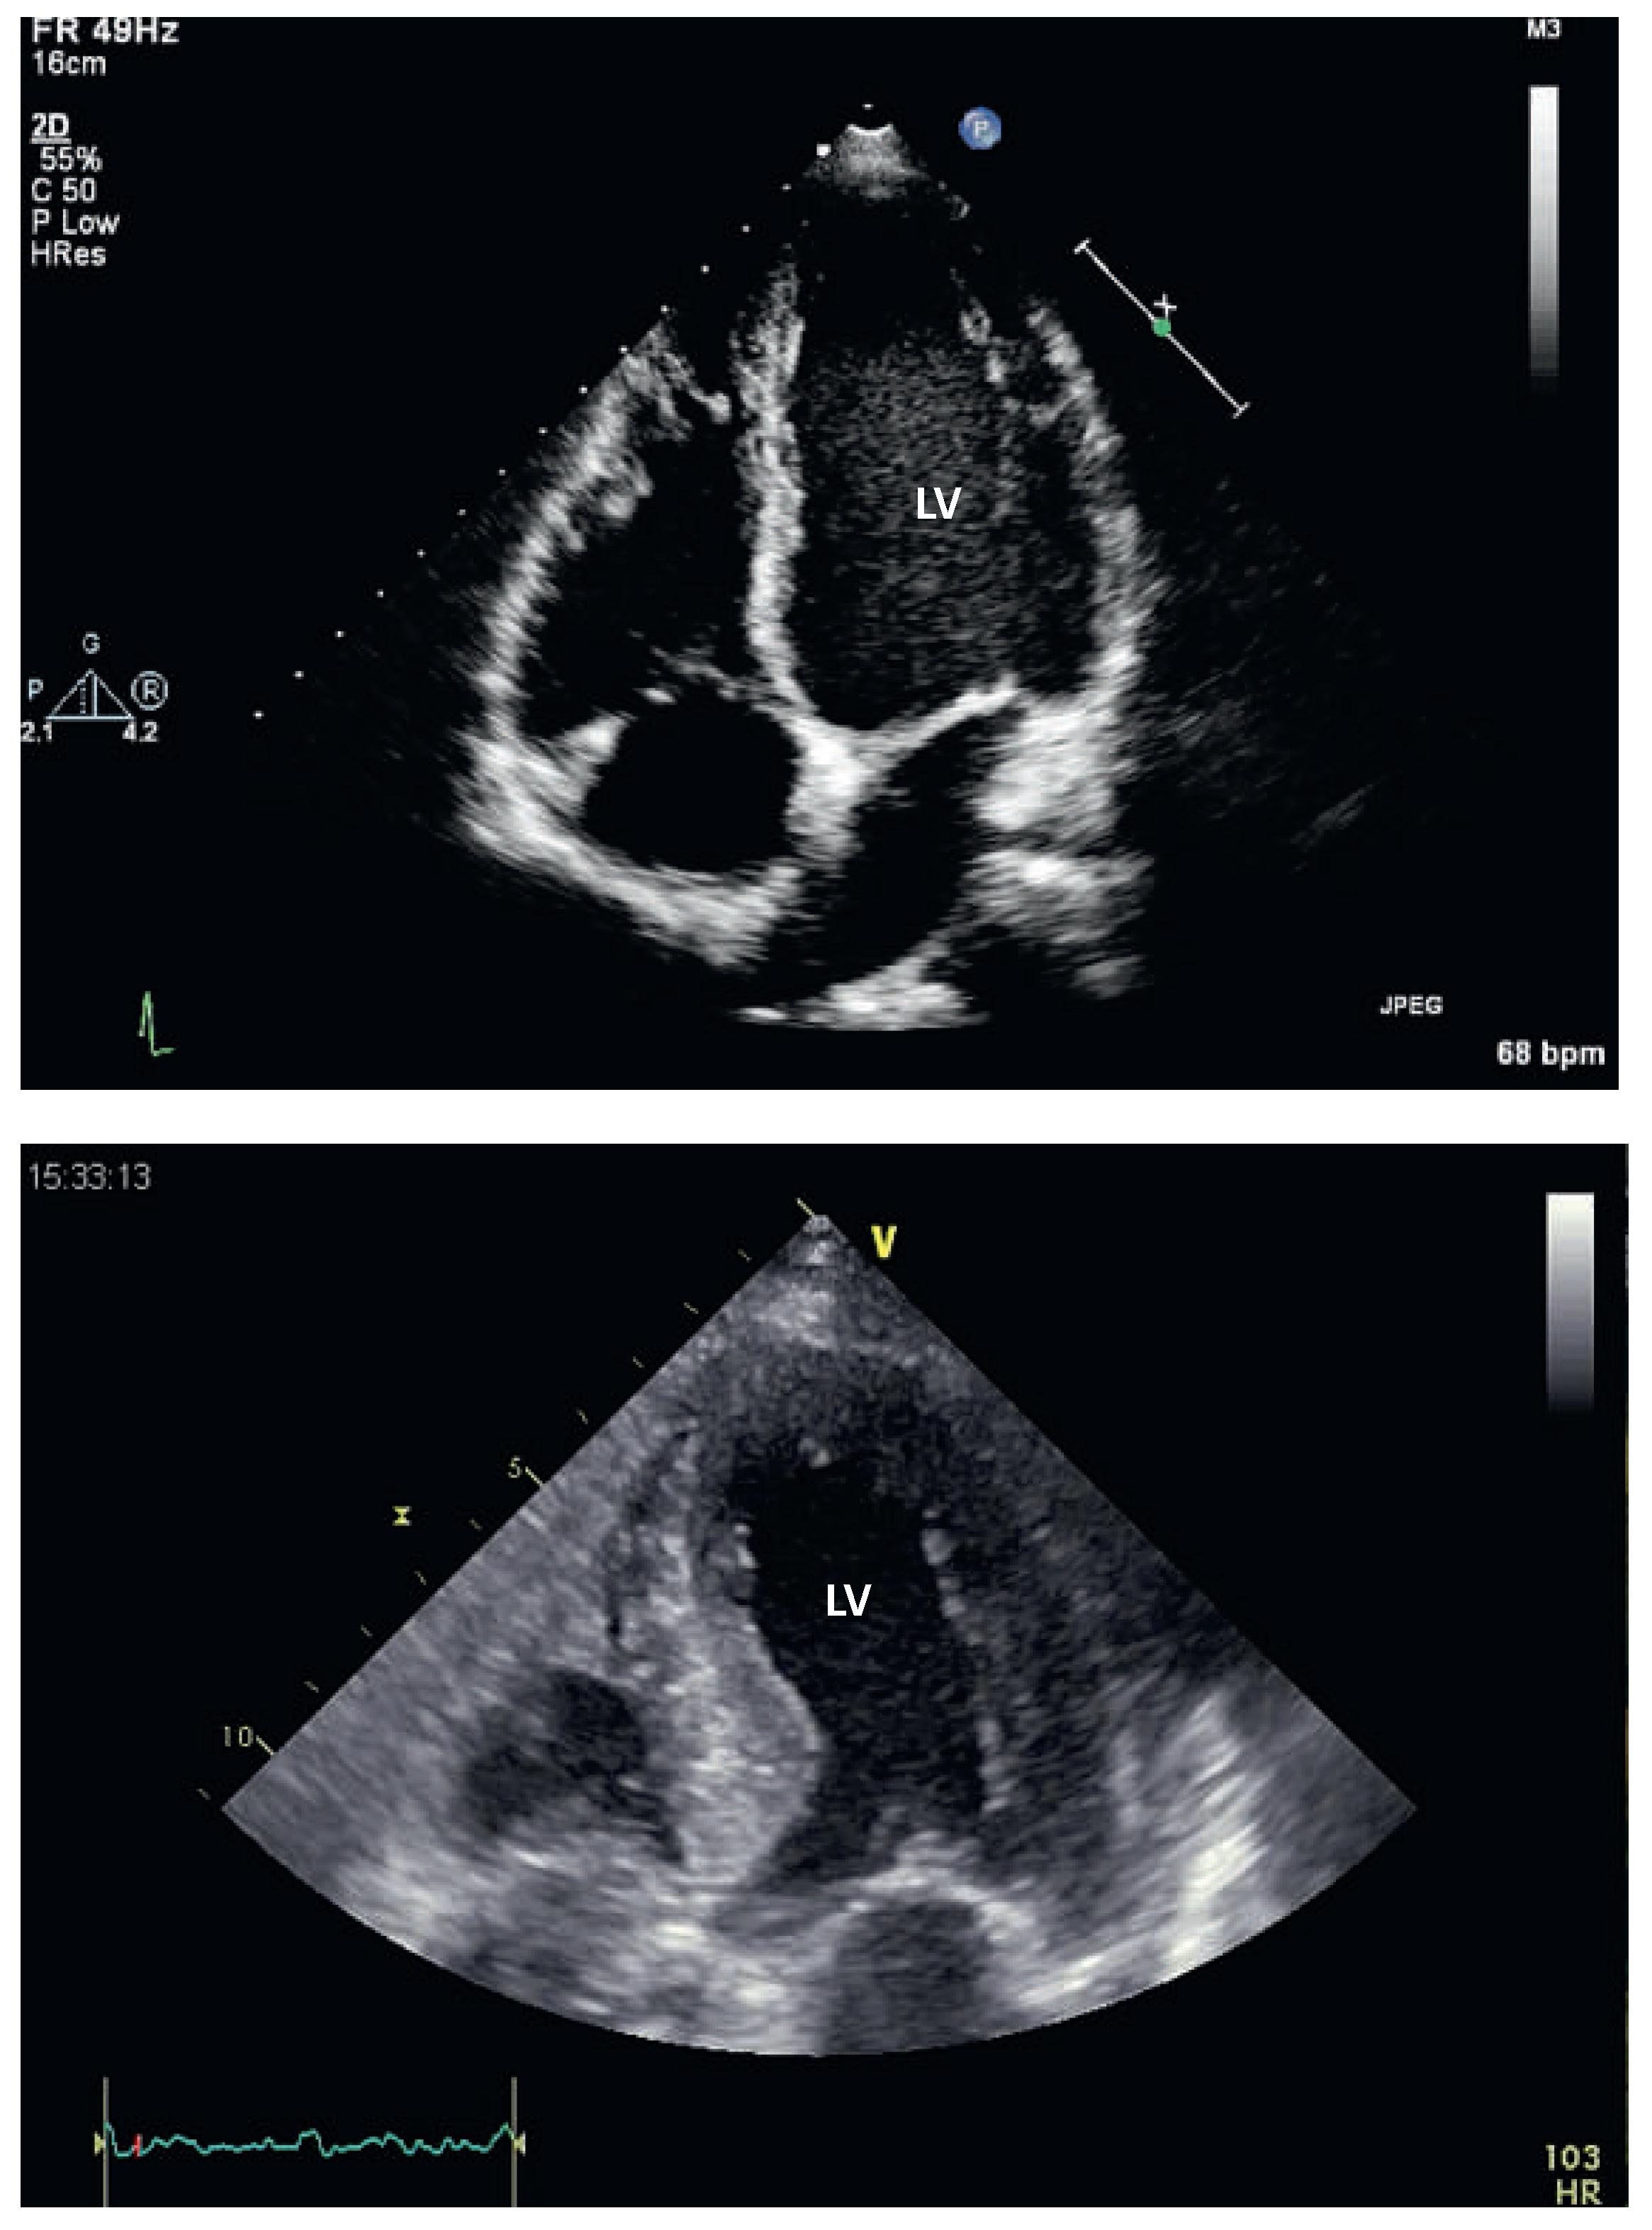

Abbildung 1.

Linksventrikuläre Hypertrophie mittels Echokardiographie. Echokardiographische Darstellung im 4-Kammer-Blick eines normalen Herzens (oben) und einer linksventrikulären Hypertrophie (unten). LV = Linker Ventrikel.

Zwei Methoden werden regelmässig in der Praxis angewendet, um eine LVH zu detektieren. Das 12-Kanal-Elektrokardiogramm (EKG) ist breit verfügbar und kostengünstig. Verschiedene anhand des EKGs berechneten Indizes erlauben die Bestimmung einer LVH. Obwohl diese Indizes eine hohe Spezifität haben, ist ihre Sensitivität ungenügend, so dass ein normaler Index im EKG eine LVH sicher nicht ausschliesst. Deutlich sensitiver zum Aufspüren einer LVH ist die Echokardiographie, die eine zuverlässige Quantifizierung der LV-Masse erlaubt (Abb. 1). Nachteile dieser Methode sind die relativ hohen Kosten, die limitierte Verfügbarkeit sowie die Untersucherabhängigkeit. Obwohl die Magnetresonanzuntersuchung des Herzens noch präziser und deutlich weniger untersucherabhängig ist, sind die Kosten und die Verfügbarkeit prohibitiv für eine systematische Anwendung. Schliesslich gibt es Hinweise, dass gewisse Biomarkerkonstellationen (z.B. niedriges C-reaktives Protein und niedriges B-Typ-natriuretisches Peptid) das Vorhandensein einer manifesten LVH in der Echokardiographie sehr unwahrscheinlich machen [4].